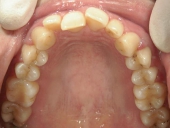

アクアシステム(透明マウスピース矯正)/上顎のみ 症例(1)

28歳 女性 浜松市中区在住  治療期間1年4ヶ月

矯正歯科 治療後 上顎